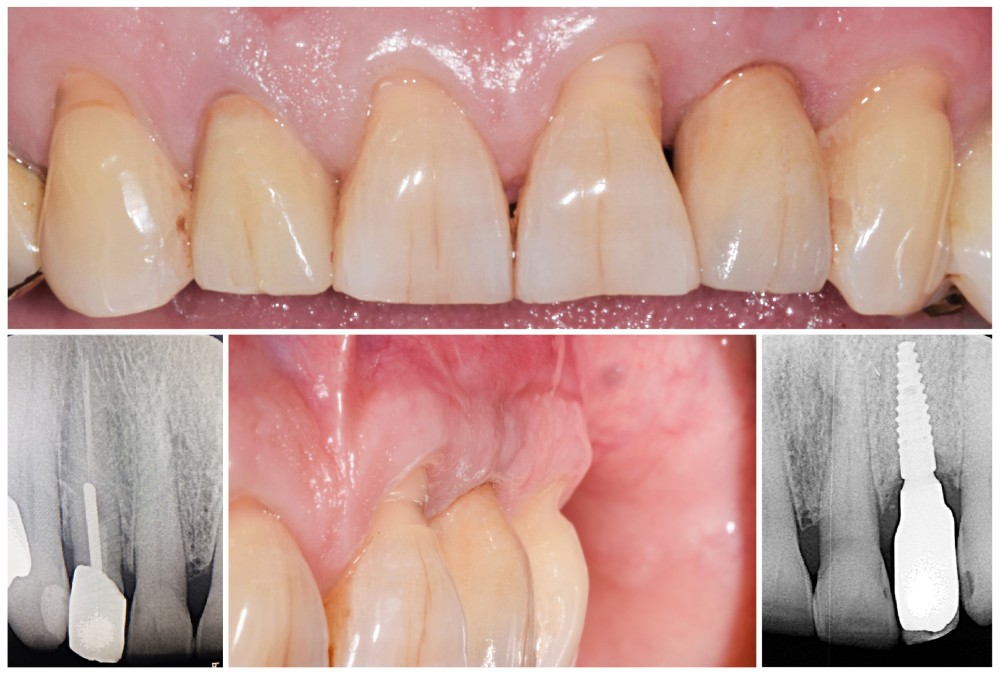

Situation initiale

Un patient de 62 ans se présente en consultation afin de réaliser les coiffes prothétiques des dents 12 et 22. La 12 présente une restauration par prothèse transitoire non adaptée. Un implant au niveau de la 22 a été posé par un autre praticien selon une technique chirurgicale en deux temps. Le praticien a adressé le patient pour la réalisation prothétique. L’option de bridge collé cantilever mono ailette n’avait pas été retenue ou proposée selon une technique chirurgicale en deux temps. Le patient souhaite rétablir l’esthétique et la fonction de ces deux dents uniquement.